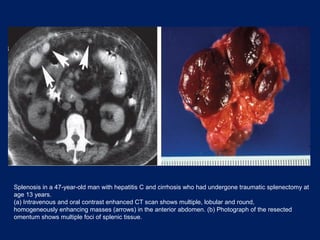

Splenosis in a 47-year-old man with hepatitis C and cirrhosis who had undergone traumatic splenectomy at

age 13 years.

(a) Intravenous and oral contrast enhanced CT scan shows multiple, lobular and round,

homogeneously enhancing masses (arrows) in the anterior abdomen. (b) Photograph of the resected

omentum shows multiple foci of splenic tissue.